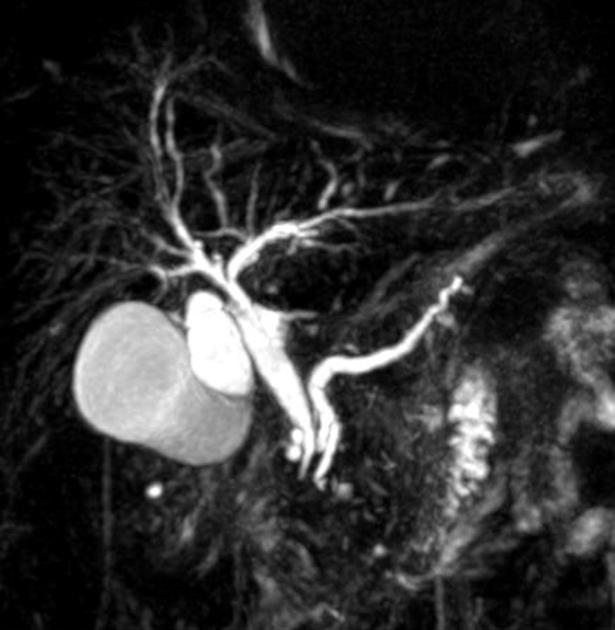

MRCP image confirms the absence of gallbladder and a normal biliary tree (Courtesy Dr. V. Penopoulos)